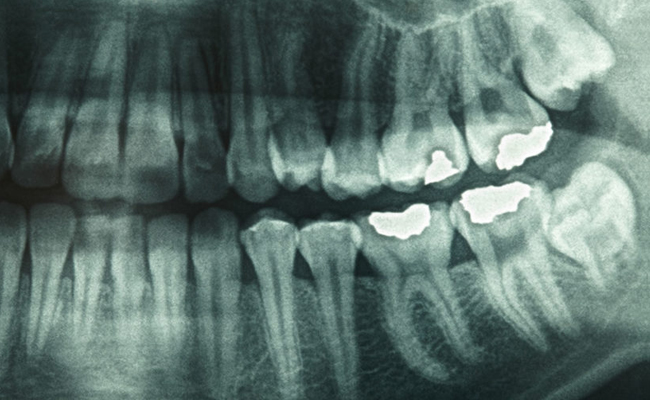

Radiography

Also Known as X-RAY. An X-ray is a quick, painless test that produces images of the structures inside your body, particularly your bones. It is used in diagnosis of caries, infection in periapical region, tooth position within the jaw.